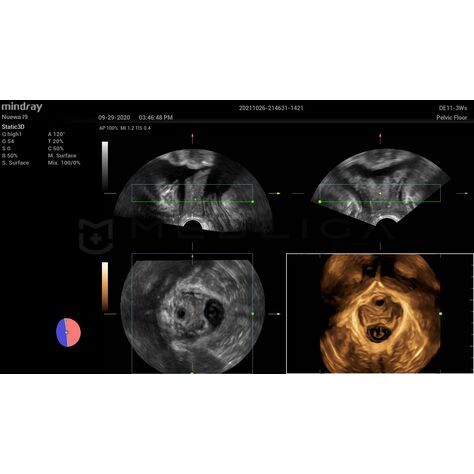

Программное обеспечение для автоматических измерений параметров и оценки функции мышц тазового дна.

Smart Pelvic - новое решение, позволяющее значительно упростить диагностическую процедуру и свести к минимуму время исследования функций мышц тазового дна. Благодаря чрезвычайно простому пользовательскому интерфейсу, программа генерирует стандартную систему координат и автоматически просчитывает все связанные измерения в течение нескольких секунд.